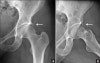

- X-ray

근육의 골부착 부위에 전형적인 석회 침착 소견으로 진단할 수 있습니다(석회 침착 소견은 4주 ~ 8개월 사이에 소실됩니다).

석회 침착이 있어도 증상이 없는 경우도 많습니다.

X-ray : 고관절 주위 석회화 건염(Calcific tendinitis around the hip)